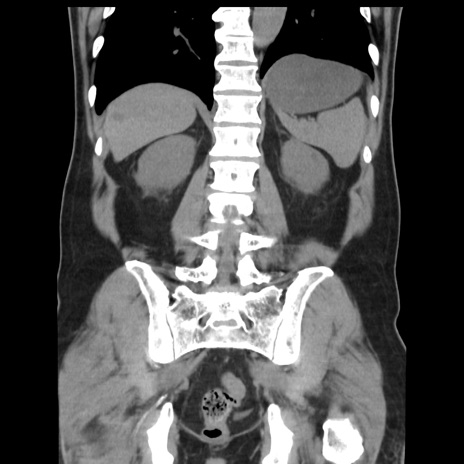

症例16(冠状断像)

【現病歴】 約1ヶ月前より間欠的に腹痛と嘔吐あり、当院消化器内科を受診したところCTで多発する肝臓のLDAを指摘され、精査中であった。以降は消化器症状は安定していたが、2日前より嘔気と腹痛があり、同日より排便・排ガスが消失した。改善認めず、 本日、救急外来を受診した。